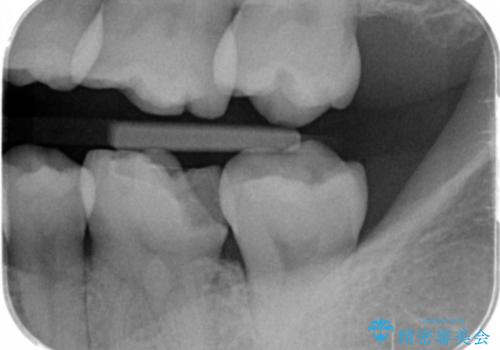

- メタルインレーが取れてしまって来院。

虫歯が再発していたので拡大鏡下で取り切った後、e-maxインレーにて治療しました。

また、一番奥の歯も古い樹脂の治療がされていたため虫歯の予防のために樹脂を取り除き、う蝕がないことを確認してe-maxインレーで治療しました。